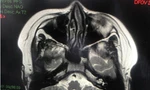

Các bác sĩ đã thực hiện siêu âm chẩn đoán kết hợp với xét nghiệm và chụp cộng hưởng từ. Kết quả cho thấy, người bệnh bị ung thư gan với khối u ở gan kích thước gần 4cm có dấu hiệu di căn. Sau hội chẩn, các bác sĩ đã thực hiện phẫu thuật cắt bỏ phần gan mang khối u kết hợp điều trị bằng thuốc ngăn ngừa di căn phát triển. Cuộc mổ đã diễn ra thành công, hiện sức khỏe bệnh nhân đang bình phục tốt và tiếp tục được theo dõi, điều trị.

Các triệu chứng ung thư gan cụ thể thường không xuất hiện trong giai đoạn đầu. Để tầm soát ung thư gan, người bệnh sẽ phải thực hiện một số phương pháp như siêu âm chẩn đoán hình ảnh kết hợp xét nghiệm đo nồng độ AFP trong máu, nội soi ổ bụng, làm sinh thiết, chụp X-quang cắt lớp và chụp cộng hưởng từ.